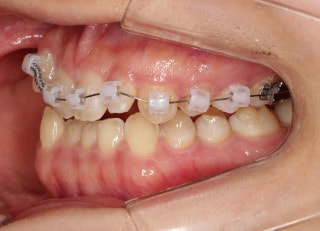

治療開始時

治療開始から25ヶ月後